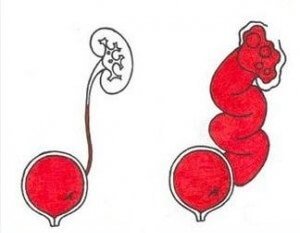

Рефлюксирующий мегауретер: Визуализация и медицинские изображения